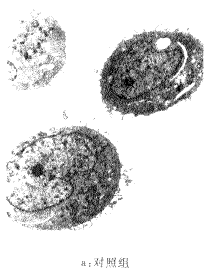

二、电镜观察SGC-7901细胞的凋亡

VES处理SGC-7901细胞48小时后电镜观察见到典型的细胞凋亡特征(图2)

图2 VES处理SGC-7901细胞的形态观察

从图2中可见,对照组没有发生凋亡的细胞有绒毛,线粒体细胞器正常,而在VES处理后的SGC-7901细胞可见染色质浓集成块状,绒毛消失,染色质固缩边集在核膜四周呈新月状小体(图2-b),并可见凋亡小体(图2-C)。